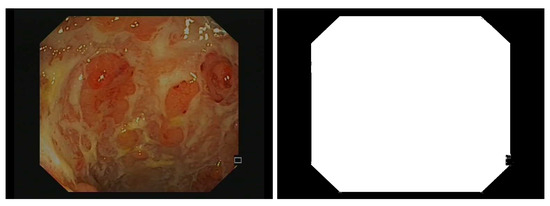

- -

3.2.1. Image Preprocessing